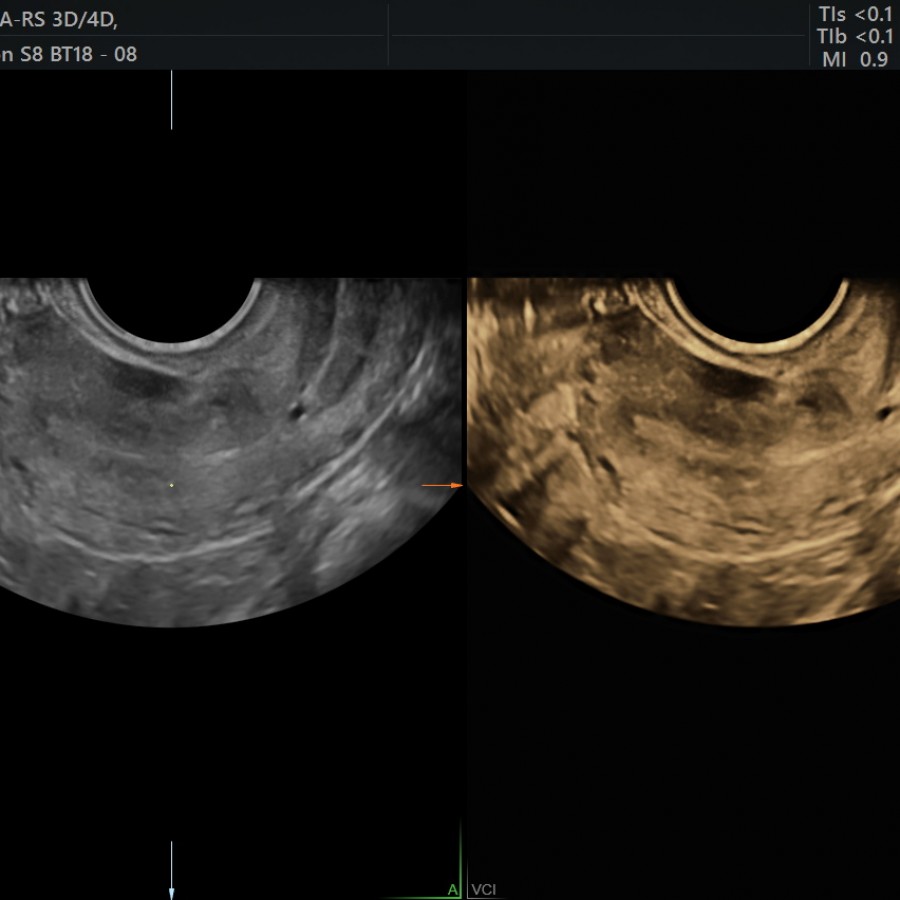

3D Ultrasound / Colour Doppler Birla Fertility & IVF Fertility Tests Ultrasound Ultrasound exam—this test can predict when ovulation will occur by. Ovarian reserve testing is a fertility test that measures if your egg count is in a typical range compared to other people your age. A doctor places an ultrasound wand into the vagina and brings it close to the pelvic organs. A saline sonogram (also referred to as a sonohysterogram,. Fertility Tests Ultrasound.